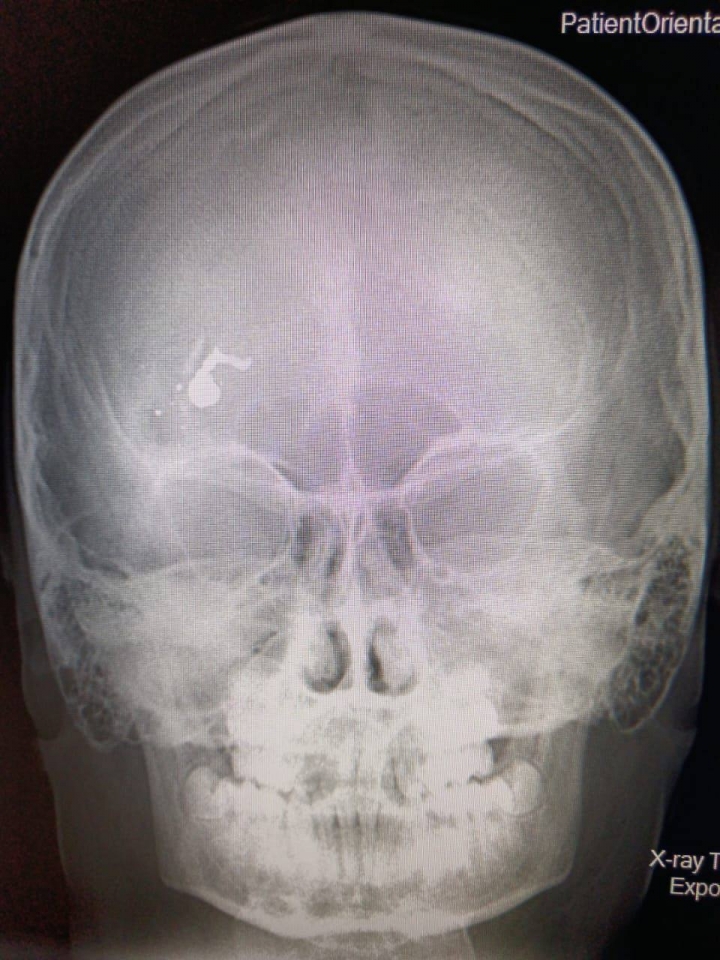

Мальчика из Дергачей доставили в районную больницу, где наличие инородного тела в лобной доле черепа подтвердилось.

После консультации с дежурными хирургом и нейрохирургом Саратовской областной детской клинической больницы ребенка решили транспортировать в областной центр.

Пострадавшего доставили в СОДКБ, и бригада хирургов незамедлительно приступила к операции, которая длилась около пяти часов.